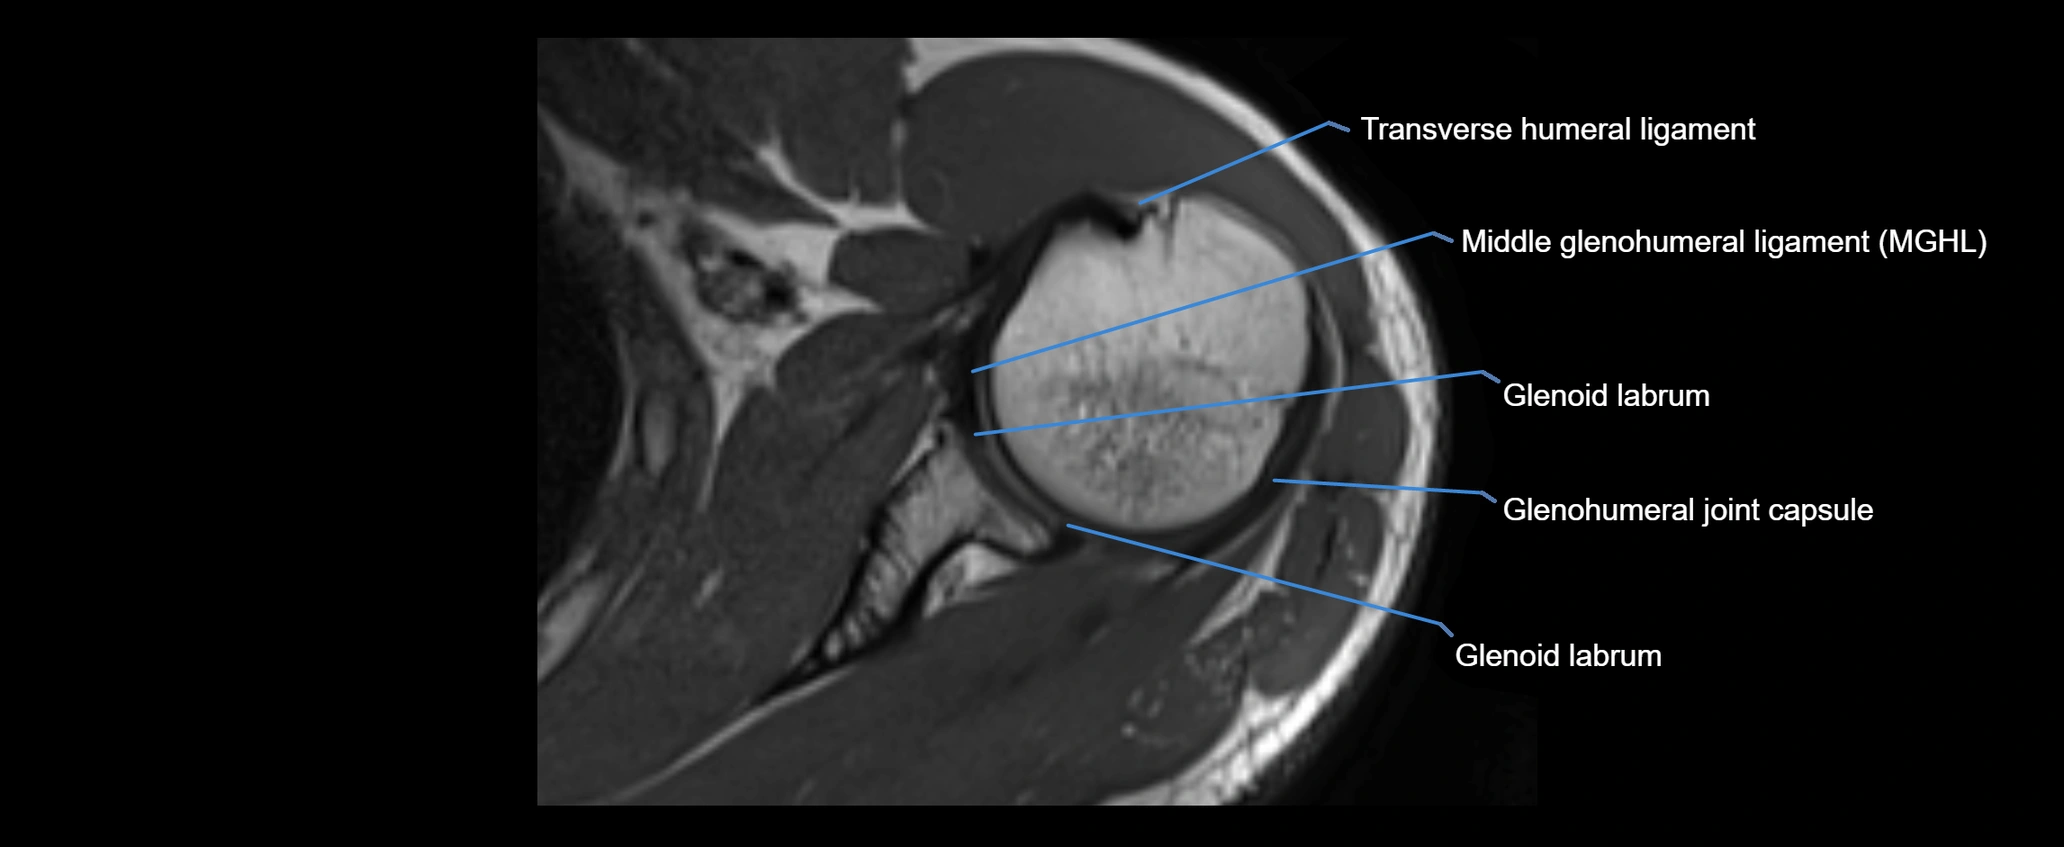

MRI images

image